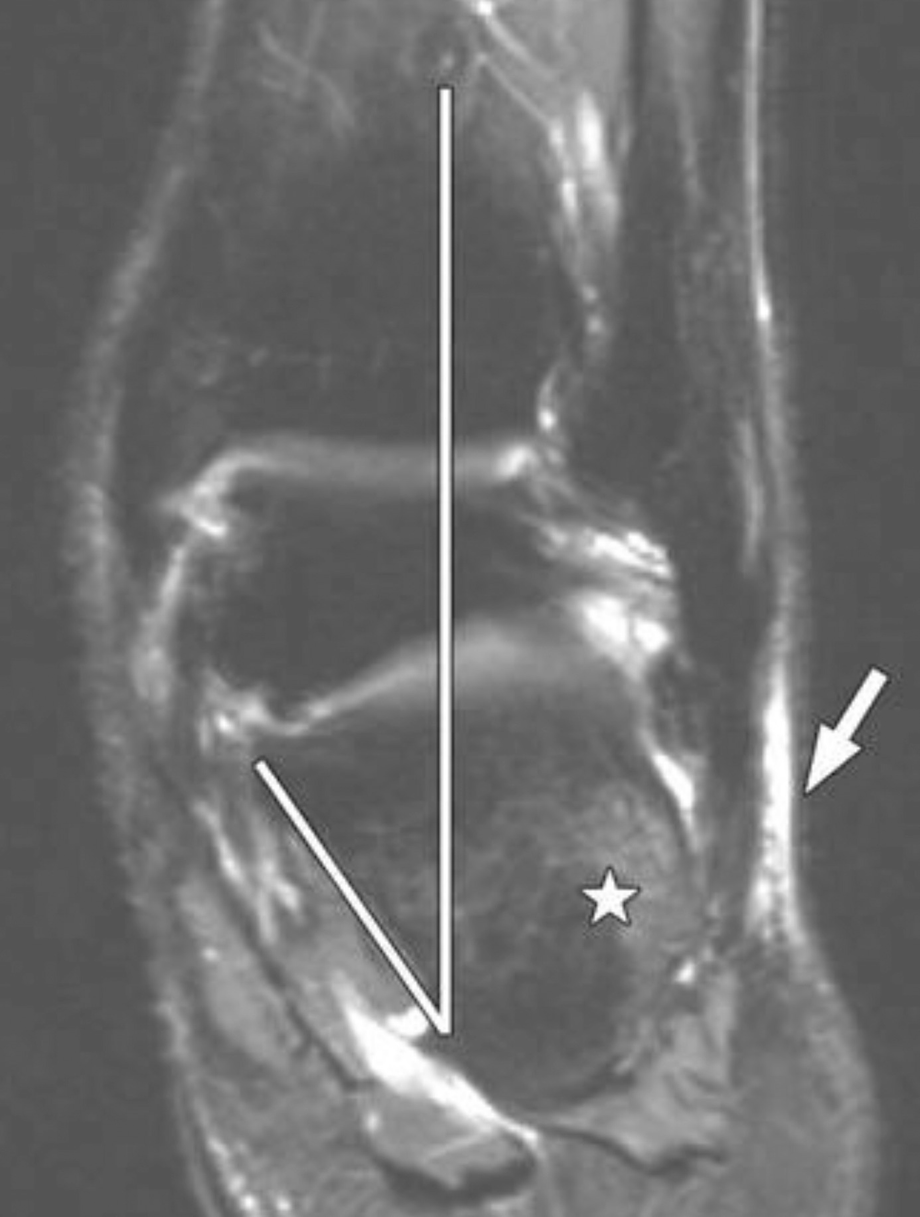

The Adult Acquired Flatfoot Springerlink